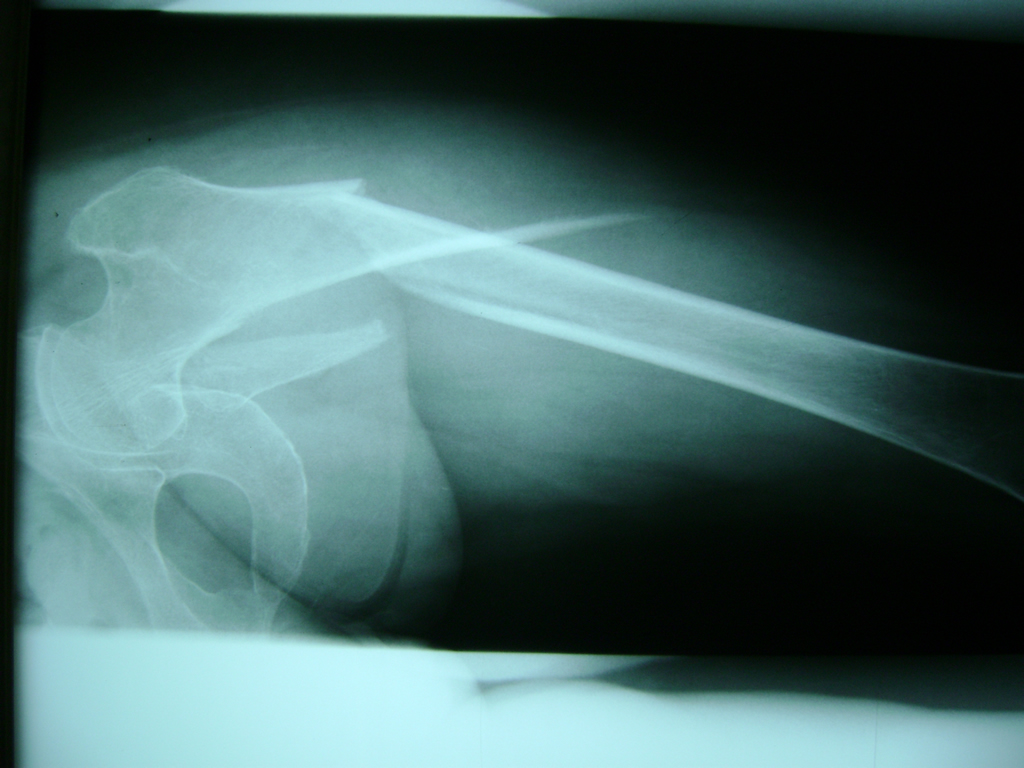

La cirugía de fractura de cadera se realiza para reparar una ruptura en la parte superior del hueso del muslo. Este hueso se denomina fémur.

Es parte de la articulación coxofemoral. Si una fractura de cadera no recibe tratamiento, es posible que deba permanecer en una silla o en la cama.

Esto puede llevar a otros problemas de salud potencialmente mortales, sobre todo si usted es una persona mayor.

A menudo se recomienda la cirugía para reparar la fractura debido a dichos riesgos.